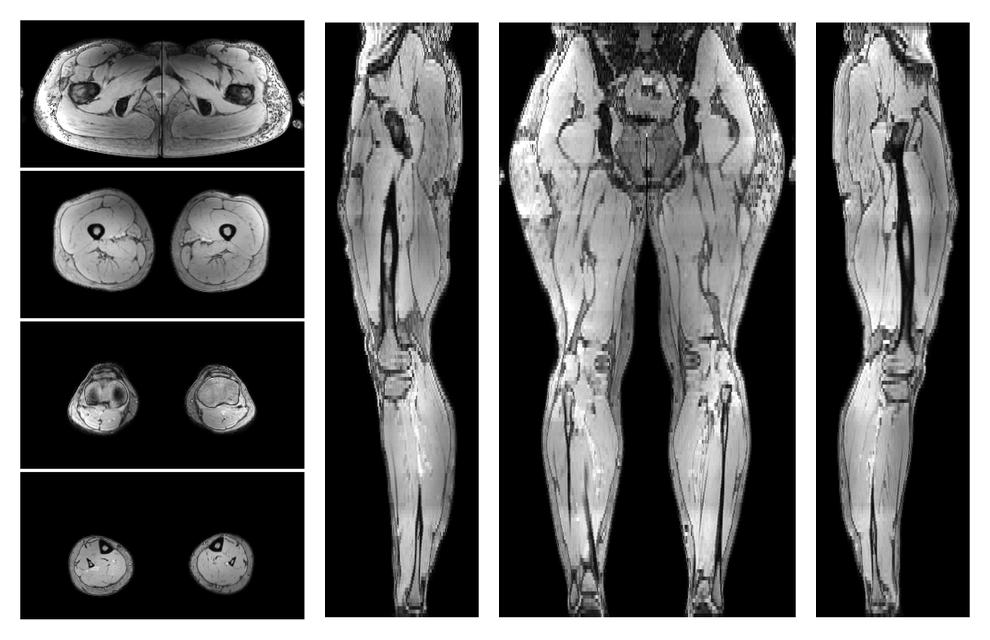

• Water only signal

The water part of the acquired multi-echo spin echo data.

Muscle segmentation

Convolution neural network based (UNET) fiber automated muscle segmentation, for information look here».

• Automated muscle and bone segmentation.

Overlay of automated muscle segmentation labels on dixon water image.